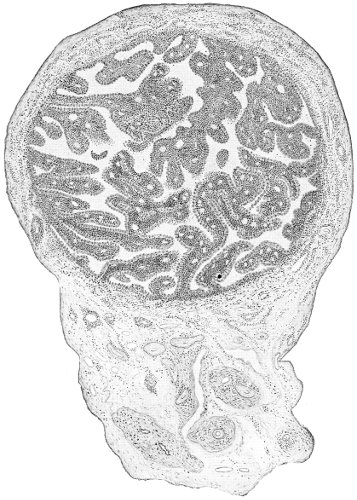

The vagina extends, as a transverse slit in the pelvic floor, upward and backward, approximately in the direction 60 of a line drawn from the ostium vaginæ to the fifth sacral vertebra. It is approximately parallel with the conjugate of the brim, so that when the woman is erect the long axis of the vagina is inclined at an angle of 60° to the horizon. The vagina is not a vertical open tube: it is a slit in the pelvic floor, in health always closed by the accurate apposition of the anterior and posterior walls (Fig. 21). The anterior vaginal wall is about 2½ inches long in a vertical mesial line. The posterior vaginal wall is about 3½ inches long. The vaginal walls are triangular in shape, being broader above than below. The shape of the normal vagina at the pelvic outlet is shown by Fig. 23. The section here shows the vaginal 61 slit of the shape of the letter H. The portions of the slit extending backward and somewhat outward are called the vaginal sulci or furrows. They are directions of diminished resistance in which tears are liable to occur.

Fig. 23.—Section illustrating the characteristic form of the vaginal cleft (Henle): Ua, urethra; Va, vagina; L, levator ani; R, rectum.] 62